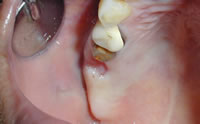

治療前

治療前の口腔内口腔内写真